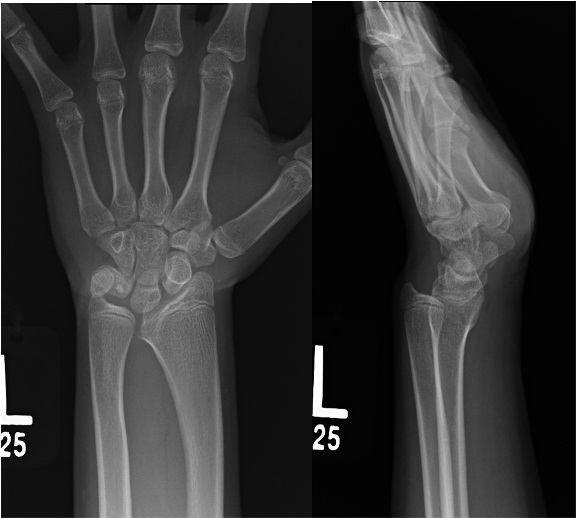

Deformity associated with madelung’s

Volar carpal subluxation

proximal radial synostosis

increased radial inclination

volar tilt

volar-ulnar tethering of vickers ligament

What is the treatment for this deformity

watch if they are young, deformity is small; assess with serial XR

Consider OR for pain or functional deformity

Physiolysis or Vickers release - open physis with progression

Radial ostotomy, vickers release, +/- ulnar ostoetomy, +/- ulnar epiphyseodesis